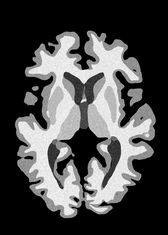

4.2 Registration to a 100 micron ex-vivo brain MRI volume

To showcase the efficacy of our method on real large scale images, we register a 250 in-vivo MRI image (Lüsebrink et al., 2017) to a 100 ex-vivo FLASH human brain volume (Edlow et al., 2019). This represents an inverse problem with more than 11.2B optimizable parameters (compared to 20M for clinical datasets), or 44.8GB of GPU memory. The entire problem does not fit on most GPUs, necessitating distributed multimodal registration. We optimize a composite transform - affine followed by a diffeomorphic mapping; details can be found in Section E.1. Multimodal deformable registration took 58 seconds on 8 NVIDIA A6000 GPUs, which is unprecedented at this resolution. Fig. 6 shows qualitative results, highlighting the ability to register highly detailed structures such as cerebellar white matter; these structures are not visible at macroscopic scales. The resultant advantages of performing registration at this scale can allow researchers to characterize the neuroanatomy at microscopic resolutions and allow morphometric analysis of cortical layers and subcortical nuclei among other structures.